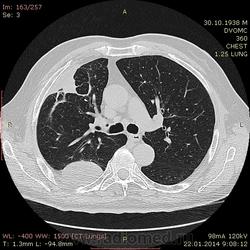

75 лет. Нарастающие боли в грудной клетке в течение 3х месяцев - со слов больного. Сейчас боль постоянная. Температуры небыло. Кашля нет. Беспокоит боль и слабость.

Плотность многоузлового образования у задней стенки от жидкостной до мягкотканной. Осумкованный плеврит или образование? Или и то и другое? Или вообще другое? Очень жду Ваших мнений.

Вопрос сложный сказать трудно, и без контрастирования трудно, и после контрастирования вопросы (скорее всего) останутся. На мой взгляд,  жидкостно-солидное образования  и осумкованные гидротораксы справа. Это может быть и первичное образование легкого, например Pulmonary Adenoid Cystic Carcinoma http://www.jkscience.org/archive/volume141/Primary%20Pulmonary%20Adenoid%20Cystic%20Carcinoma%20with%20Lumbar%20Vertebral%20Metastasis%20Response%20to%20Gefitinib.pdf но могут быть и  метастазы какой-нибуль кистозной опухоли, например, околоушной железы.

Андрей Юрьевич, как вы считаете похожи ли изменения в S3 на инфаркт легкого - треугольная форма, широко прилежит к грудной стенке, не прослеживаются бронхи....и как результат - плевральный выпот вдоль задней стенки осумковался ну и может быть за 3 месяца частично организавался - отсюда и частично солидная плотность. Не похоже на правду?

Да, очень похоже (и скорее всего, так и есть), но считаю это дополнением к основному заболеванию